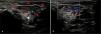

Presentamos el caso de una lactante de dos meses que presentó hinchazón progresiva en la región preauricular desde el nacimiento. Se observó una coloración azulada en la zona. No hubo ningún otro hallazgo clínico o analítico, como fiebre o malnutrición. Se llevó a cabo una ecografía de la glándula parótida por diagnóstico preliminar de parotiditis aguda y hemangioma infantil. La ecografía mostró un aumento significativo del tamaño y de la vascularización en la parótida izquierda. La parótida derecha tenía una apariencia normal (fig. 1). La paciente fue diagnosticada de hemangioma infantil, ya que no había datos de infección, iniciándose tratamiento con propranolol. A los tres meses, tanto el tamaño como la vascularización del hemangioma habían disminuido (fig. 2).